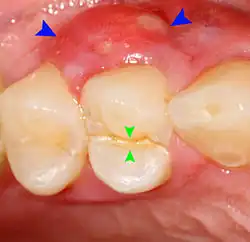

Decay (green) with apical abscess (blue) Decay (green) with apical abscess (blue)